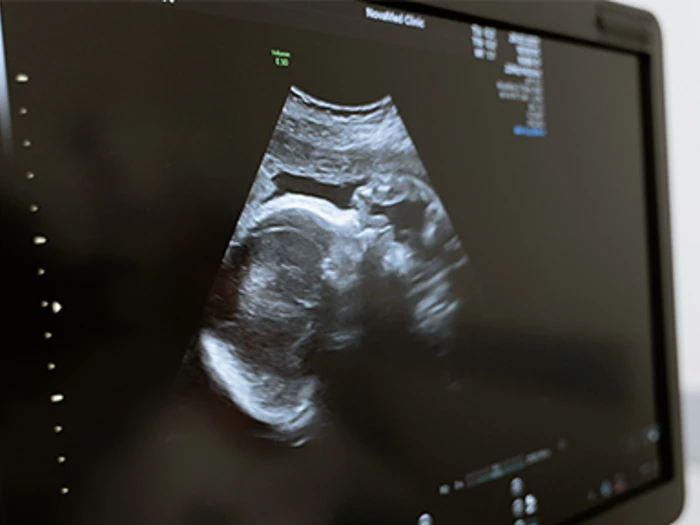

The market for ultrasound devices is rapidly expanding, particularly as technological advances allow for smaller, cheaper, and more portable devices to be developed. However, no publicly available guidance currently exists on the characteristics that ultrasound devices must possess to meet minimum and optimal requirements for obstetric use. The World Health Organization (WHO) has identified this as a priority area for Target Product Profile (TPP) development.

This project aims to develop a new TPP for obstetric ultrasound devices, to assist in driving the implementation of the WHO 2022 recommendations on antenatal care for a positive, person-centred pregnancy experience and guiding procurement of new devices for obstetric use.